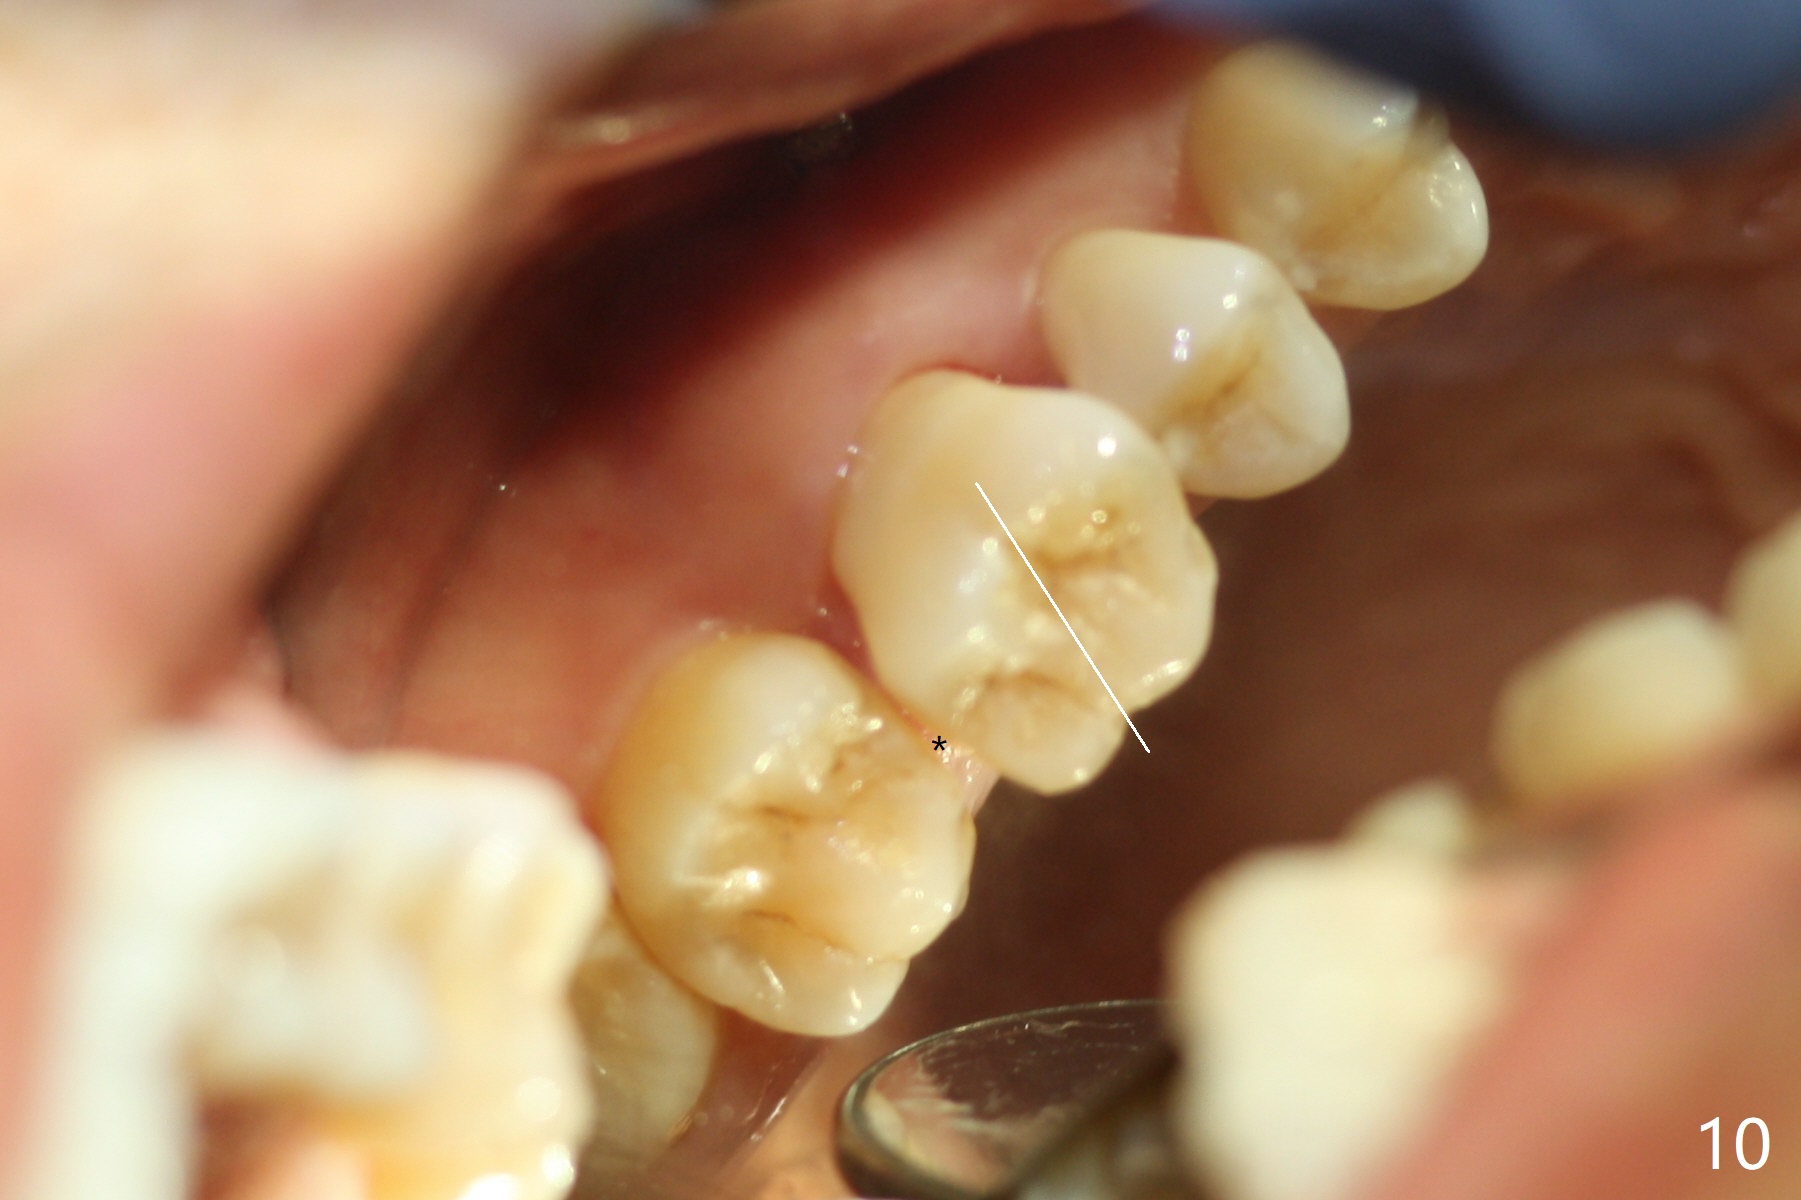

It looks as if the tooth #3 is blocked by the neighboring teeth. The proximal surfaces are reduced 1.5 months post orthodontic intrusion. Fourteen days later, the gap exists distal (Fig.10 *). It appears that the power chains placed on the natural groove of the tooth (white line) mesializes the tooth. Then the power chains are placed mesial to the mesiopalatal cusp by placing 2 of composite (Fig.11); one month later, the distal gap closes (Fig.12). The patient feels less pressure against the teeth anterior to the tooth #14. At the same time, the latter appears to have been intruded. The tooth appears to have been intruded radiographically 4 months post retraction (Fig.13).